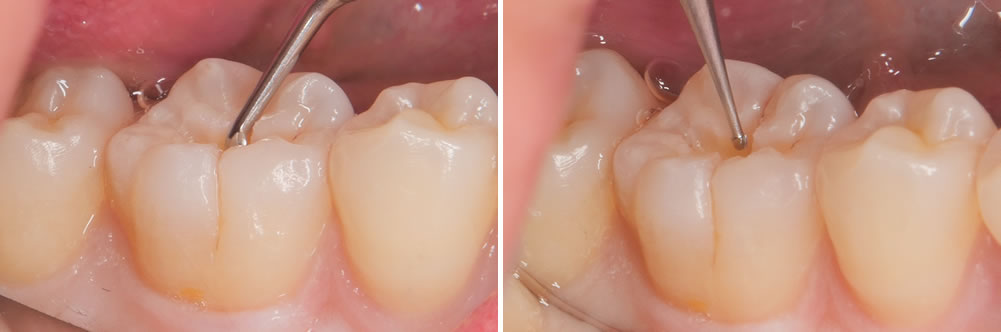

う蝕検知液を用いて丁寧に虫歯を取り除いていきます。

さらに奥にある虫歯は、より小さな器具を用いて削る範囲が大きくなりすぎないようにします。

酸処理

内部の虫歯を取り除いた状態です。接着力を上げるため酸処理を行いました。